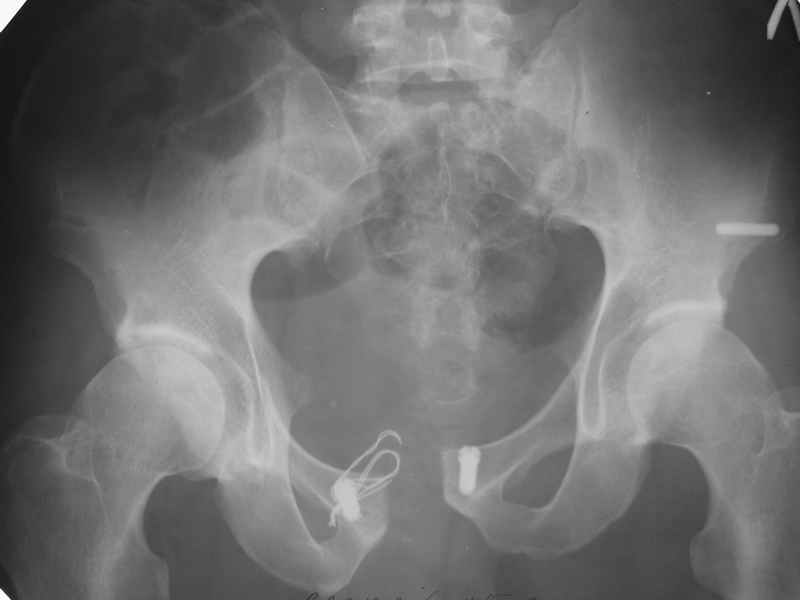

Re: Разрыв симфиза

МЯМ> Неудачное место вы выбрали. Проблема давно и просто решена дедушкой

МЯМ> Мюллером: два шурупа и серкляж.

Что-то такое подразумевается? См. приложение...